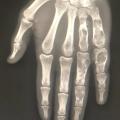

Anatomie des gaines synoviales des tendons fléchisseurs des doigts

INFECTIONS DES TISSUS MOUS

CELULLITE SOUS-CUTANEE

BOURSE SYNOVIALE

Phlegmon de l'index

Phlegmon